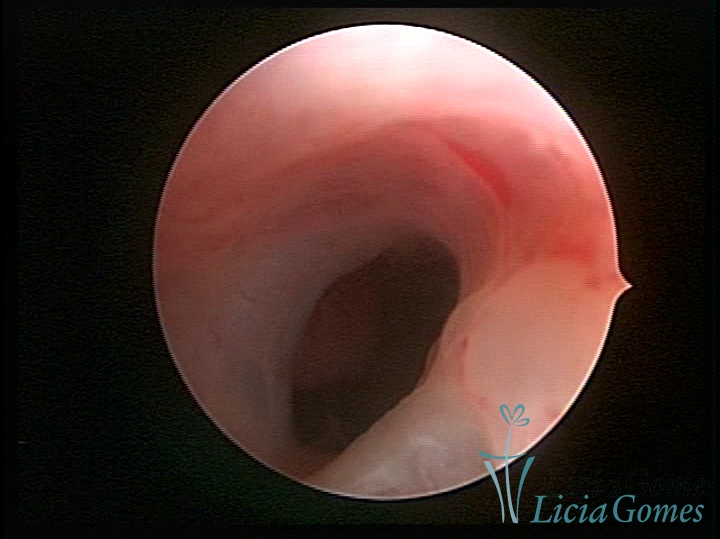

• SINÉQUIA TIPO FIBROMUSCULAR